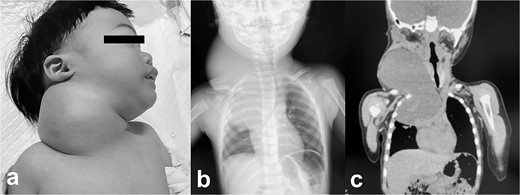

Pathologic findings on the first administration. The tumor size in the cervical region was quite large and there may be a risk of airway system compression. (a) physical finding, (b) chest X-ray, (c) plain computed tomography.